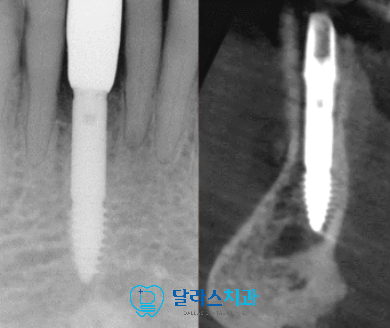

최종보철이 완료된 모습입니다.

만약 임플란트나 연결부위인 어버트먼트에 문제가 발생하였을 경우

해결을 할 수 있도록 최종보철은 나사구멍을 제작하여 수리보완이 가능하도록 제작하였습니다.

좁은 골폭에서도 좌우,앞뒤로 치우치는 곳이 없는지 x-ray와 CT를 통해서 확인해보면

주변으로 고르게 치조골이 위치하는 중앙에 식립이 잘 된 것을 확인할 수 있습니다.